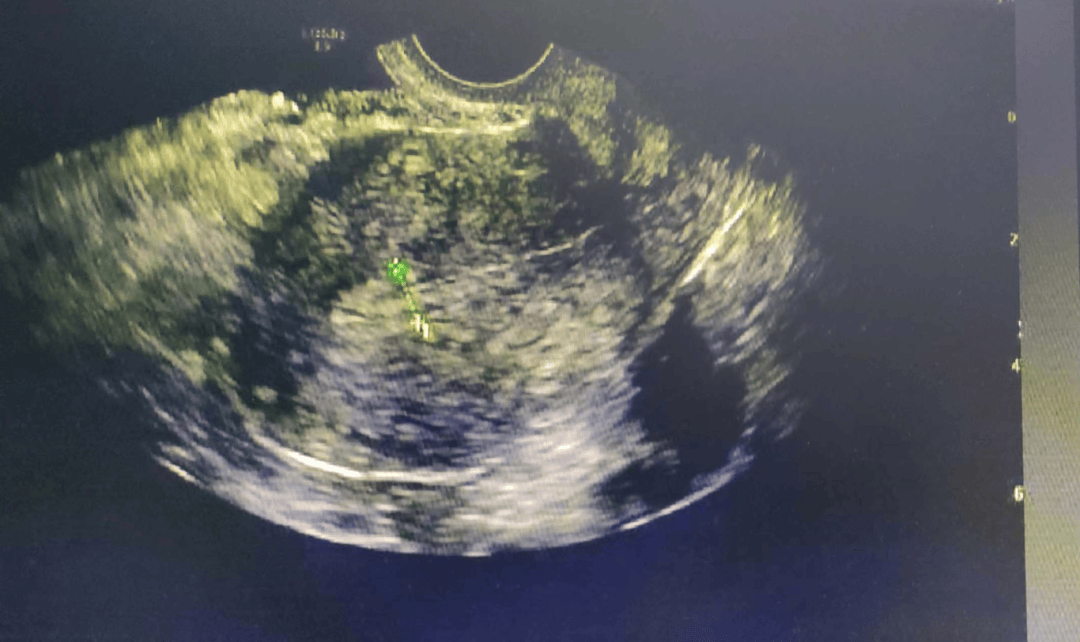

3、妇科彩超主要检查女性的子宫卵巢盆腔以及输卵管等部位具体来说子宫通过彩超可以观察子宫的大小形态位置以及子宫内膜的厚度和回声情况,判断是否存在子宫肌瘤子宫腺肌症子宫内膜息肉等子宫疾病卵巢彩超能够清晰显示卵巢的大小形态以及卵泡的发育情况,有助于诊断卵巢囊肿卵巢早衰多囊;妇科彩超是一种通过超声探头对女性生殖系统相关部位进行检查的方法,主要检查以下内容检查部位彩超可针对子宫卵巢输卵管等关键生殖器官进行评估子宫方面,可观察其大小形态位置及内膜厚度,辅助诊断子宫发育异常或内膜病变卵巢方面,能评估卵巢体积形态卵泡数量及囊肿情况,识别多囊卵巢综合征或;一检查目的妇科彩超的核心目标是评估子宫卵巢输卵管等器官的结构与功能具体包括观察器官结构检测子宫和卵巢的大小形态位置是否正常,判断是否存在先天性发育异常或后天性改变检测病变筛查子宫肌瘤卵巢囊肿子宫内膜息肉等常见疾病,明确病变的性质大小及位置评估血流情况通过彩色;妇科彩超一般不需要空腹具体原因如下妇科彩超的核心目的是检查女性生殖系统,包括子宫卵巢输卵管等器官的结构与功能这些器官位于盆腔深处,其成像质量主要受膀胱充盈程度的影响,而非消化系统的状态适度充盈的膀胱可形成良好的“透声窗”,使超声信号更易穿透,从而清晰显示子宫轮廓卵巢形态及盆腔;2 输卵管与卵巢检查输卵管和卵巢是妇科彩超的重点观察区域超声可发现输卵管积水因炎症或粘连导致输卵管扩张,内含液性暗区,这类病变可能影响受孕或导致慢性腹痛对于卵巢,彩超能识别卵巢囊肿包括生理性囊肿和病理性囊肿,如巧克力囊肿畸胎瘤等,并测量其大小边界及内部回声,辅助判断囊肿性质3 盆腔检查盆腔积;妇科彩超能够清晰地显示子宫的大小形态以及内膜厚度,帮助医生判断是否存在子宫肌瘤子宫腺肌症等病变同时,它还可以检查卵巢的大小形态,以及是否存在囊肿多囊卵巢综合症等疾病这些疾病的早期发现对于治疗和预后至关重要早期妊娠诊断彩超检查在妊娠早期具有重要地位,能够确定胚胎的位置胎囊的。

4、妇科彩超不全是阴超,它包含阴超和经腹部彩超两种检查方式一妇科彩超的两种检查形式妇科彩超是通过超声波技术对女性生殖系统进行影像学检查的方法,其检查途径分为经阴道阴超和经腹部两种经阴道彩超需将探头置入阴道内操作,适用于有性生活史的女性经腹部彩超则通过体表扫描完成,适用于无性生活;妇科彩超可辅助诊断多种妇科疾病,具体如下一子宫相关疾病1子宫肌瘤彩超可清晰显示肌瘤位置肌壁间黏膜下或浆膜下大小及数量,并观察其是否压迫周围组织2子宫腺肌病表现为子宫均匀性增大,彩超可见肌层增厚回声不均,部分患者合并腺肌瘤3子宫内膜息肉宫腔内出现中强回声团;未婚女性通常可以做妇科彩超妇科彩超是观察女性生殖系统包括子宫卵巢输卵管等的常见检查方法,其安全性与婚姻状态无直接关联未婚女性可通过适当的准备和操作安全完成检查,医生会根据患者情况选择检查方式1经腹部彩超这是未婚女性的首选方式,无需插入探头,通过体外扫描即可观察子宫和附件。

5、彩超检查是一种无创性检查方法,主要用于观察子宫和附件的情况,包括子宫肌瘤卵巢囊肿等病变然而,对于阴道炎等妇科炎症的检查,彩超则无法直接显示在这种情况下,医生通常会建议进行白带常规检查,通过实验室检测来判断是否存在炎症及其具体类型值得注意的是,正规医院的医生在进行检查和诊断时,会根据;妇科彩超主要用于检查女性生殖系统健康,具体检查内容如下1检查目的妇科彩超的核心目标是检测女性生殖系统的多种病变针对子宫,可发现子宫肌瘤子宫腺肌病子宫内膜息肉等结构异常针对卵巢,能识别卵巢囊肿多囊卵巢综合征及卵巢肿瘤等问题针对输卵管,可评估其通畅性,排查积水或粘连此外,还可;做彩超能检查出以下多种妇科病盆腔炎彩超可清晰观察到受检者盆腔内是否存在炎症性改变,例如盆腔组织充血水肿等表现同时,能准确测量盆腔积液的含量,这对判断炎症的严重程度有重要意义此外,彩超对于协助观察盆腔内子宫输卵管卵巢等器官的形态大小及位置等情况也有一定作用,有助于医生全面。